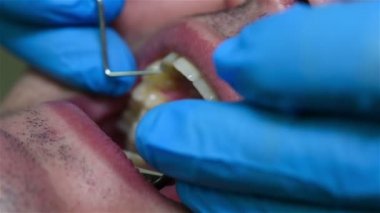

Yakın plan, dişçi diş tedavisinden önce kadın bir hastaya anestezi enjekte eder..

Eser Sahibi: Denys Diedov